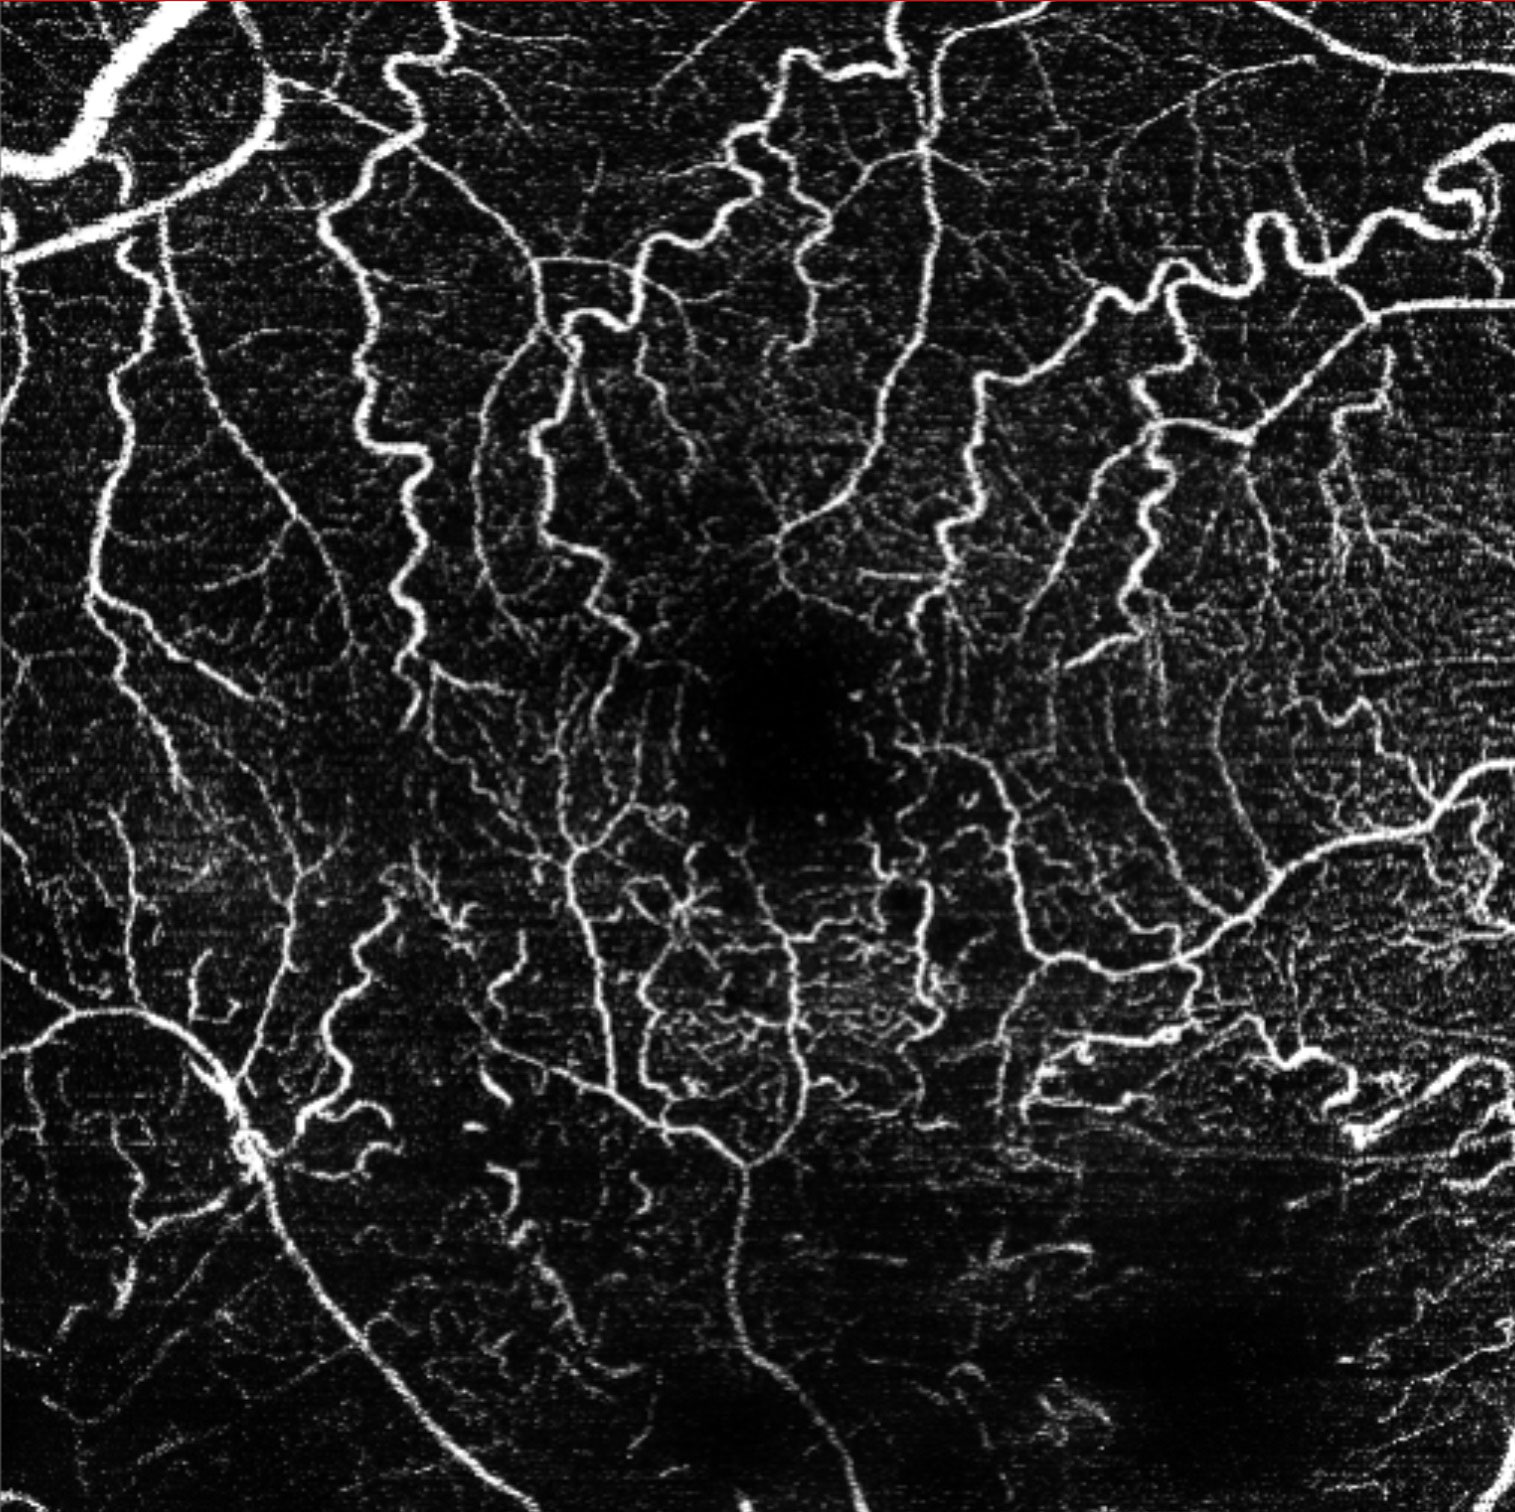

Offering the ideal speed-quality ratio for OCTA, 125 kHz allows you to increase your throughput without any clinically relevant loss in image quality in comparison to the current 85 kHz scan speed. The fast acquisition of images allows for visualization of flow, even in miniscule vessels, while minimizing artefacts, resulting in sharp and detailed images of the capillary network. Additionally, you can decrease chair time when you speed up acquisition with the Glaucoma Module Premium Edition in your glaucoma workflow, if applicable.

125 kHz – A fast scan speed for improved workflow and high OCTA image quality.